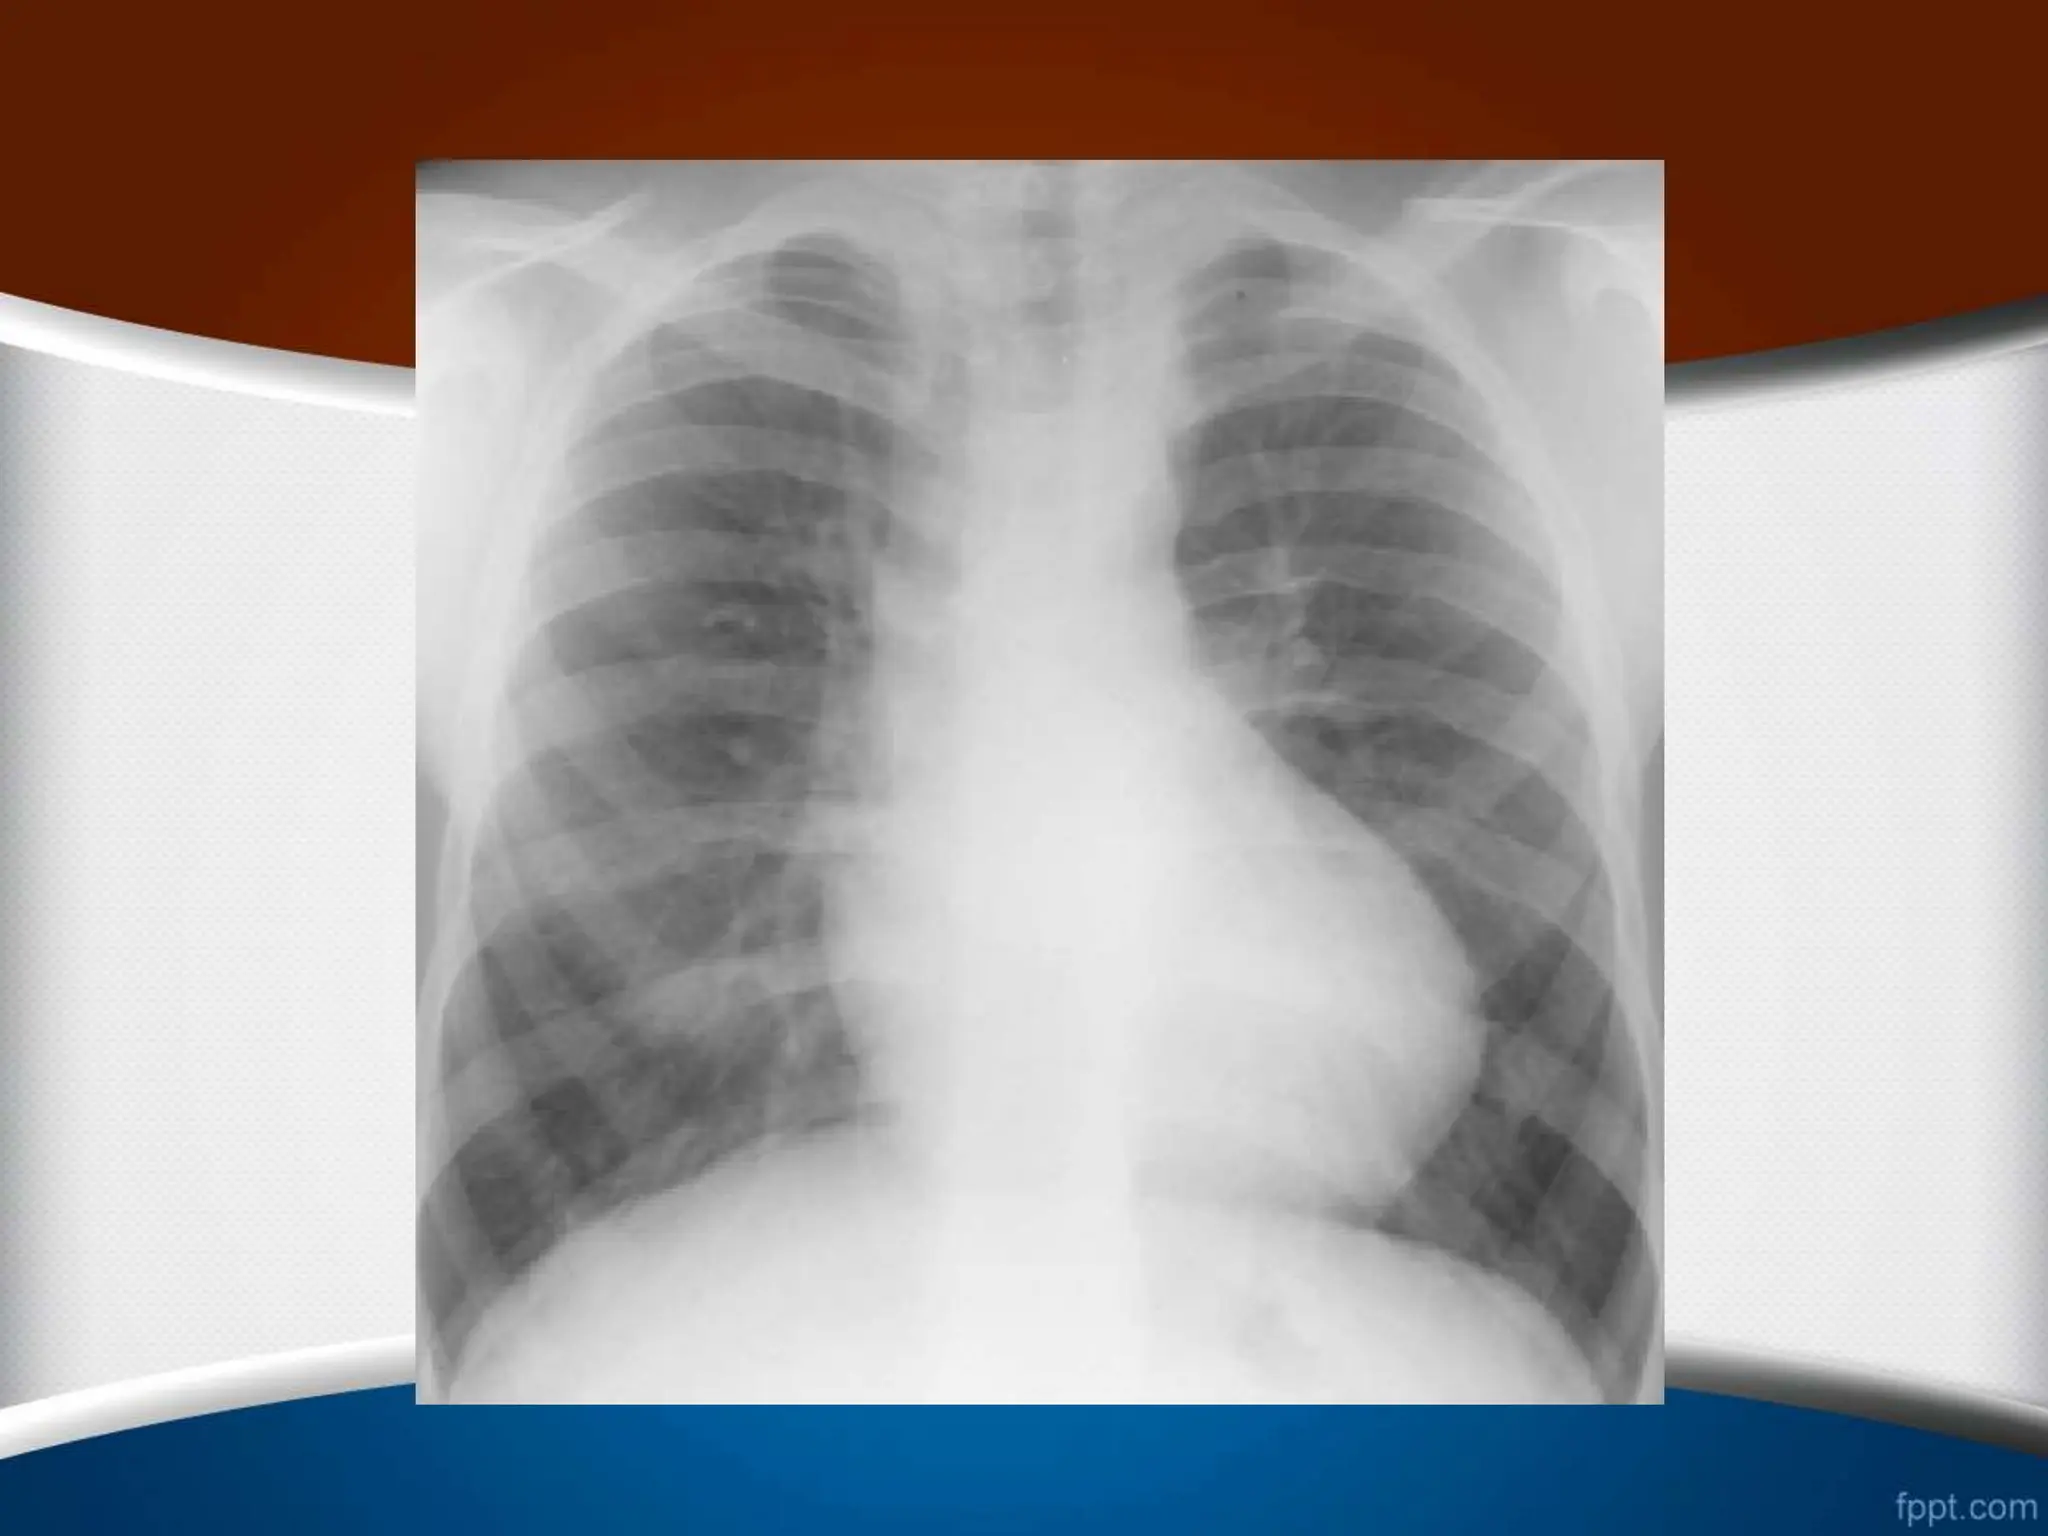

‫کاردیوتوراسیک‬ ‫نسبت‬ ‫نرمال‬ ‫حالت‬ ‫در‬

‫افراد‬ ‫در‬

‫از‬ ‫کمتر‬ ‫بالغ‬

50

%

‫است‬

‫این‬ ‫مسن‬ ‫افراد‬ ‫و‬ ‫کودکان‬ ‫در‬

‫نسبت‬

‫تا‬

55

‫باشد‬ ‫می‬ ‫قبول‬ ‫قابل‬ ‫هم‬